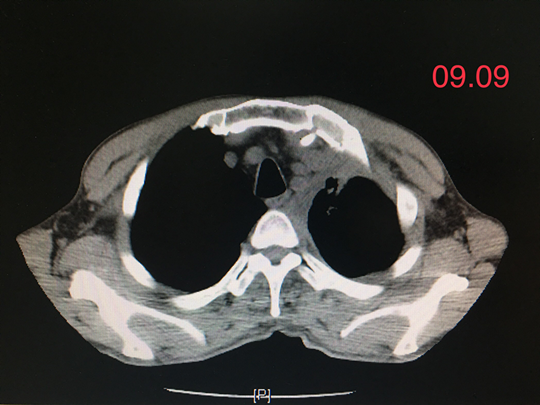

就这样过了两个月,王先生再次复查胸部CT,发现其左肺肿瘤病灶基本消失了,治疗效果非常好!